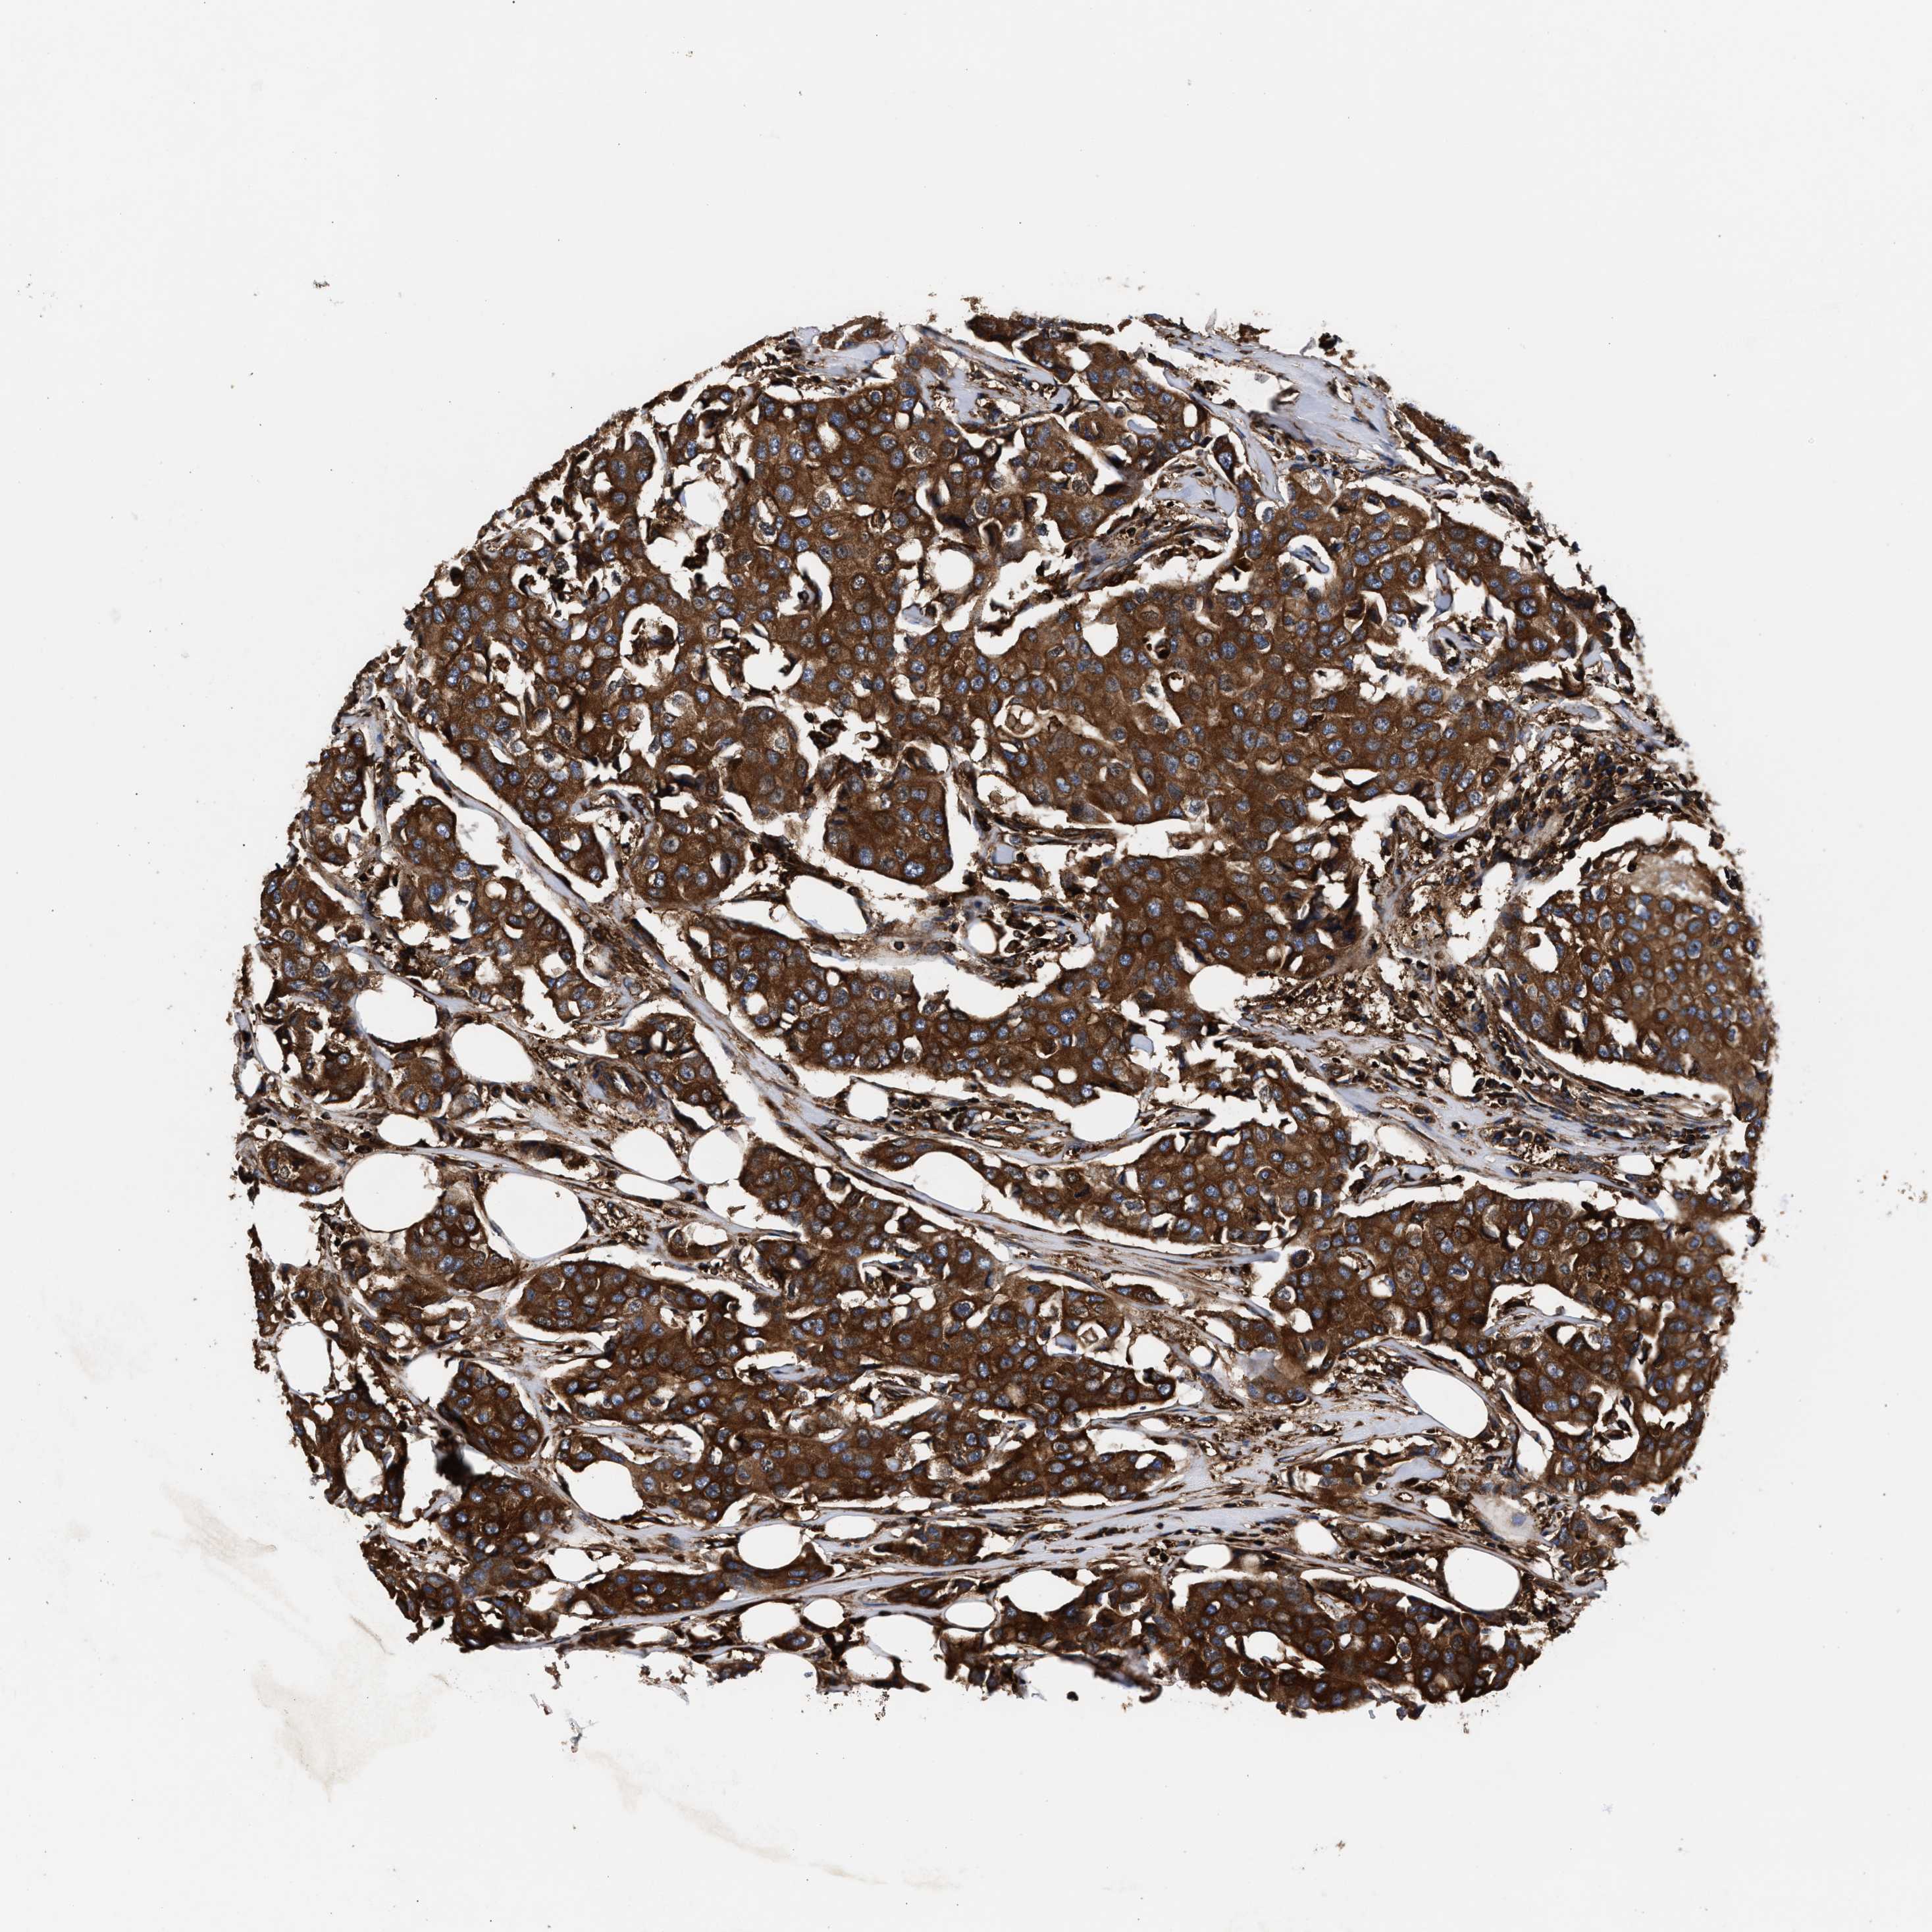

BRCA TCGA BRCA VALIDATION PROTEIN EXPRESSION

ANTIBODIES

AND

VALIDATION